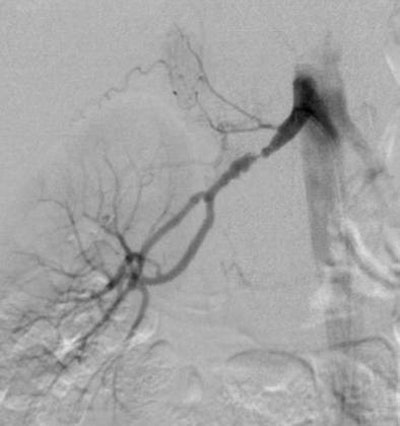

![]() |

| DSA in the same patient showing periadventitial-type fibromuscular dysplasia. |

"DSA is the gold standard for detection of RAS, but invasive catheter angiography is best reserved for therapeutic intervention," Moorthy said. He recommended MRA as the first imaging modality of choice if cost was not a constraint, but that DSA should be used as the first diagnostic test only in cases with a high index of suspicion.